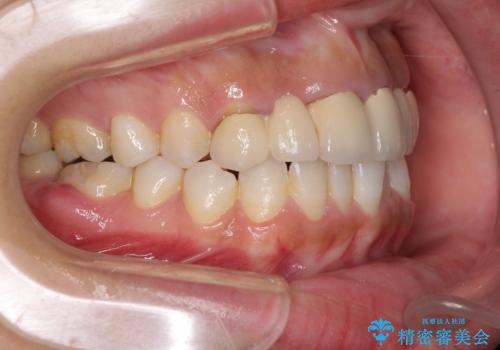

- 審美的ではない上の前歯とデコボコの下の前歯、歯茎が腫れている奥歯を気にして来院された患者様です。

根管治療の必要な歯がいくつかあるため、まずは根管治療を行い、その後インビザラインにて矯正治療を行うこととしました。

矯正治療後に前歯をセラミックブリッジに、奥の銀歯はセラミックインレーやPGAインレー(ゴールドインレー)にて補綴・修復治療を行うこととしました。

矯正治療により下顎前歯を整列させたため、上顎前歯のセラミックブリッジを補綴することで口元を少し下げることができました。

ヒトの目線がいつも口元に向けられているように感じることがなくなり、患者様には大変満足していただきました。